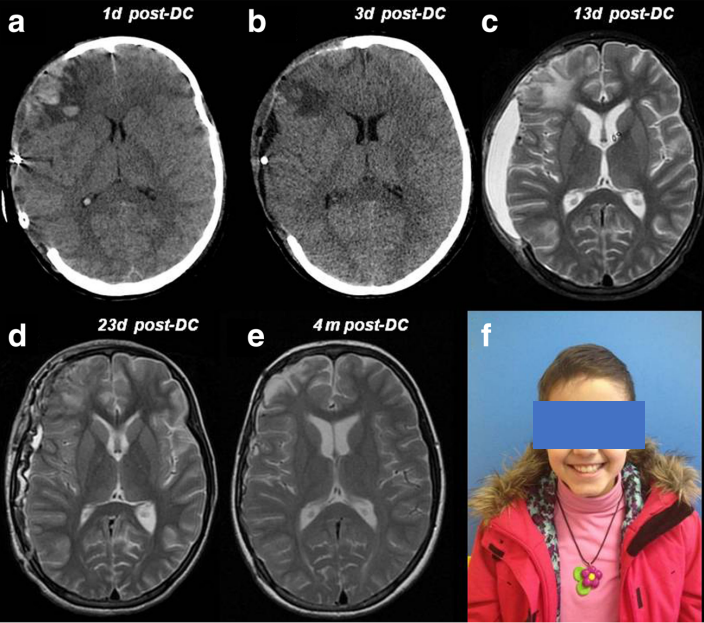

圖 1:一名 11 歲女孩遭受嚴(yán)重頭部損傷,接受右側(cè)腦半球去骨瓣減壓術(shù)(a - c),并在初次手術(shù) 20 天后進(jìn)行自體骨瓣替換(d、e)。在 3 年隨訪中,神經(jīng)狀況良好(格拉斯哥結(jié)果量表 GOS 5 分),顱骨成形術(shù)成功(f)。